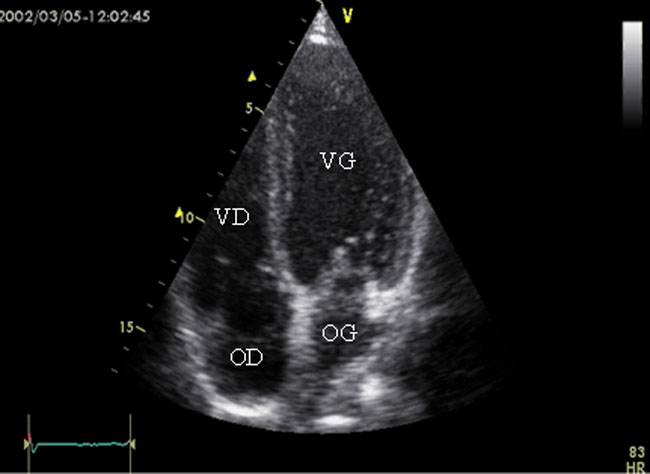

- 7 - Echocardiographie - Doppler